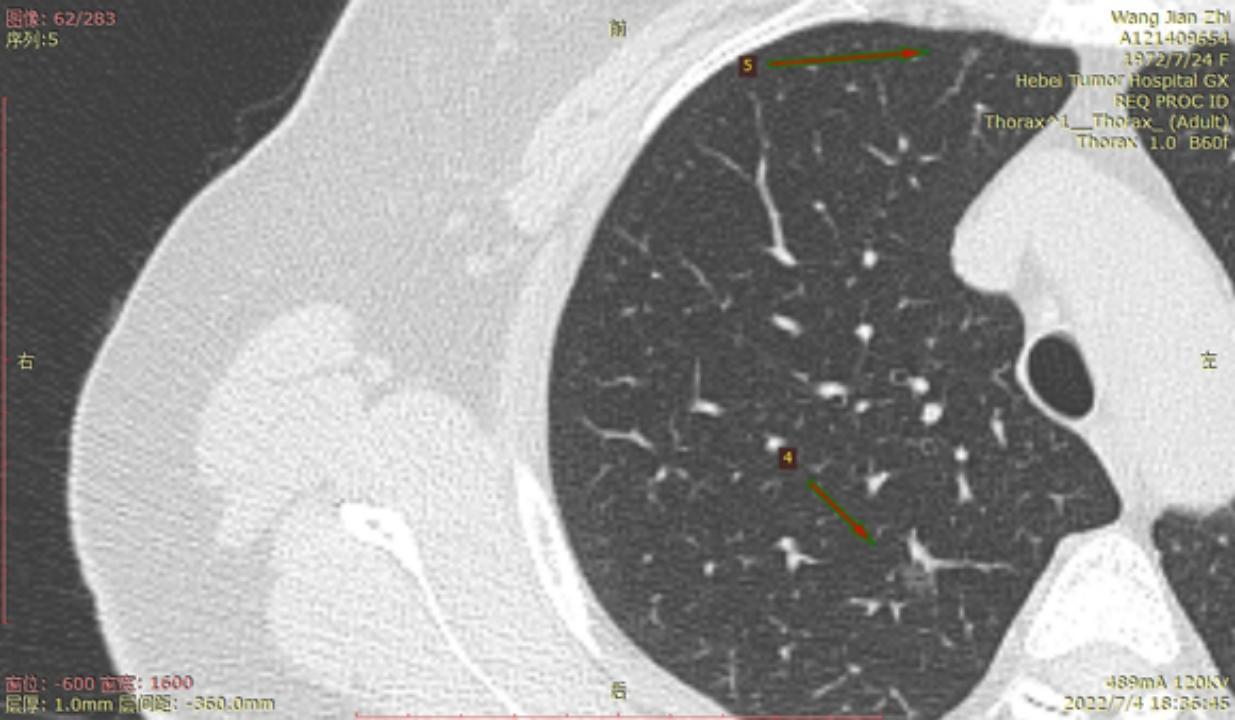

结4-5

右侧至少5枚以上的微浸润或原位腺癌,大的两枚结节微浸润,建议半年内把右侧5mm以上或者有危险的结节一网打尽。左侧结节还安全,安心随访